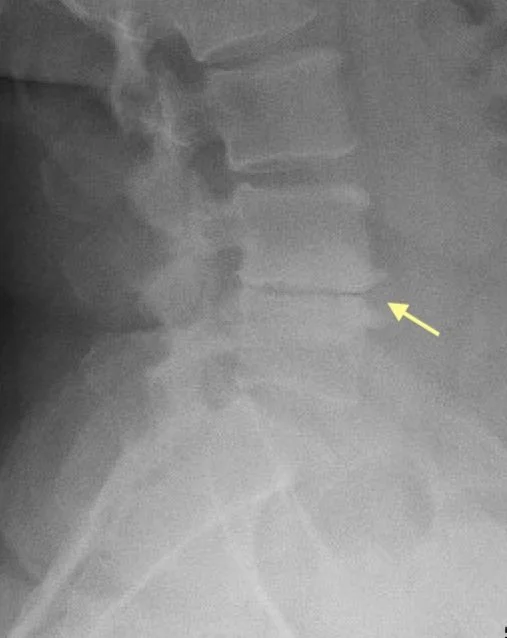

Lateral Lumbar X-ray severe arthritis bone on bone

Severe degenerative disc disease with bone-on-bone arthritis.